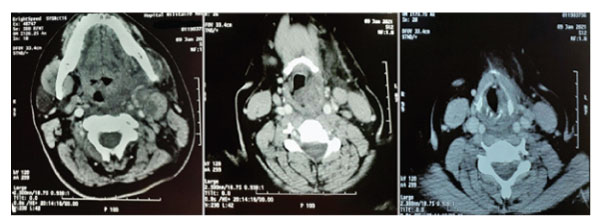

Flexible fibre optic Naso-pharyngoscopy revealed a gross oedema of the left hemilarynx that extended from the epiglottis to the left ventricular cord and left arytenoid cartilage. (Figure 1-a). Vocal cords were partially covered by the oedema. Nasopharynx and oropharynx were slightly edematous as well. Cervical CT scan found: a left pharyngo-laryngeal wall thickening, extended on 6 cm from cavum to glottis, with ipsilateral upper internal jugular lymphadenopathy with central necrosis and perilesional edema (Figure 2). Lab investigations showed hyperleukocytosis with 12000/mm3 and high C-reactive protein (CRP): 372 mg/L. Erythrocyte sedimentation rate (ESR) was raised at 49 mm/h. A fine-needle cytopuncture with histopathological examination revealed ganglionic lymphoid parenchyma with foci of eosinophilic necrosis surrounded by a palisade of lymphocytes, without epithelioid or giant cells, consistent with histiocytic necrotizing lymphadenitis of Kikuchi-Fujimoto (Figure 3).

Figure 2: Tomodensitometry images showing a left lateralized pharyngo-laryngeal wall thickening, extended from cavum to glottis, with ipsilateral upper internal jugular lymphadenopathy with central necrosis and perilesional edema.